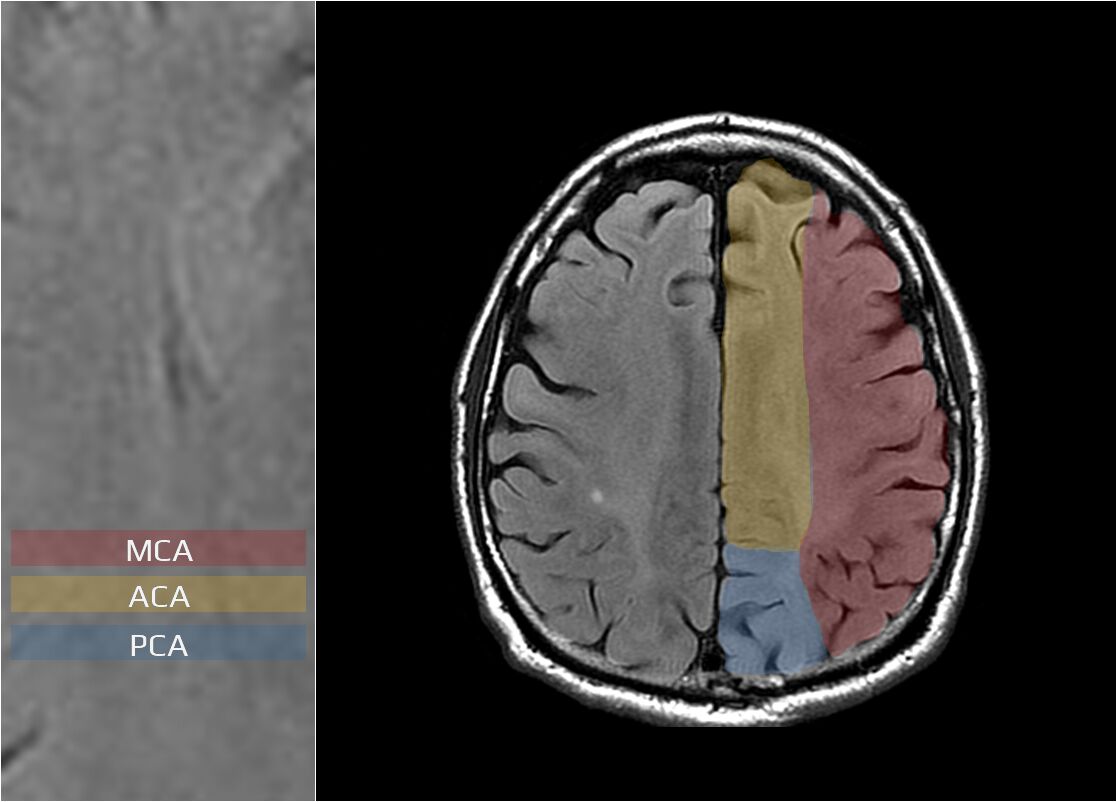

(B) 前大腦動脈梗塞型中風

(C) 中大腦動脈梗塞型中風

ACA、MCA、PCA的範圍如圖: